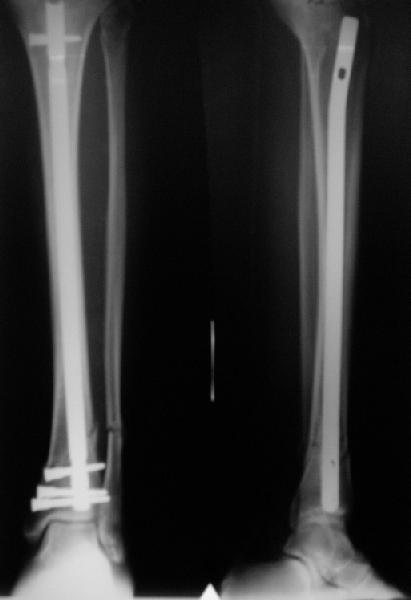

Alexander Chelnokov 22 Май 2006, 00:35

Сделали все-таки стержнем. На всякий случай просверлил дополнительное проксимальное отверстие, так что получилось три 45-градусных винта.

В дистракторе провеи спиц поболше в прокисмальном отделе, чтобы не разобщить фрагменты при сгибании колена. Комментарии и критика приветствуются.

We proceeded with nailing using a small wire distractor, with few wires at the proximal end to prevent displacement with forced knee flexion. Images attached. Comments and critics are welcome.